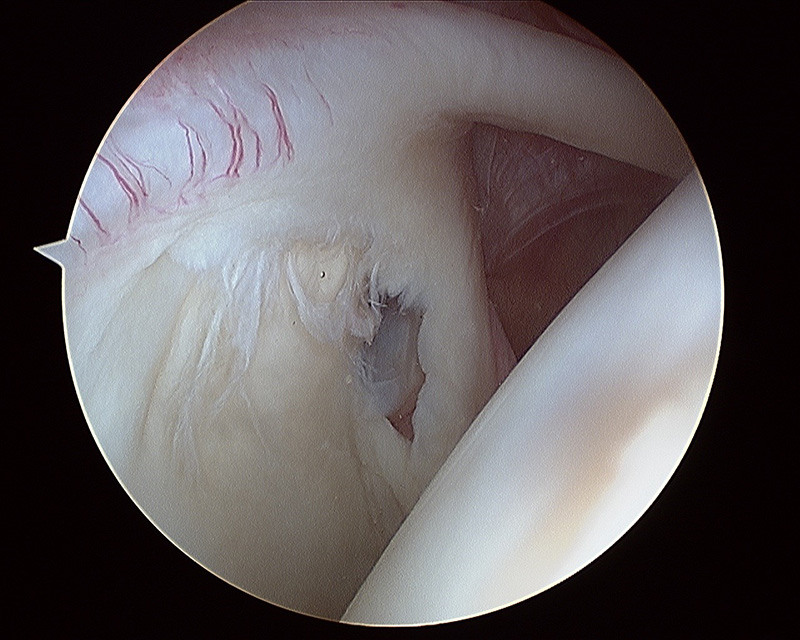

Foramen sublabral del hombro

Shoulder sublabral hole

- Foramen sublabral del hombro